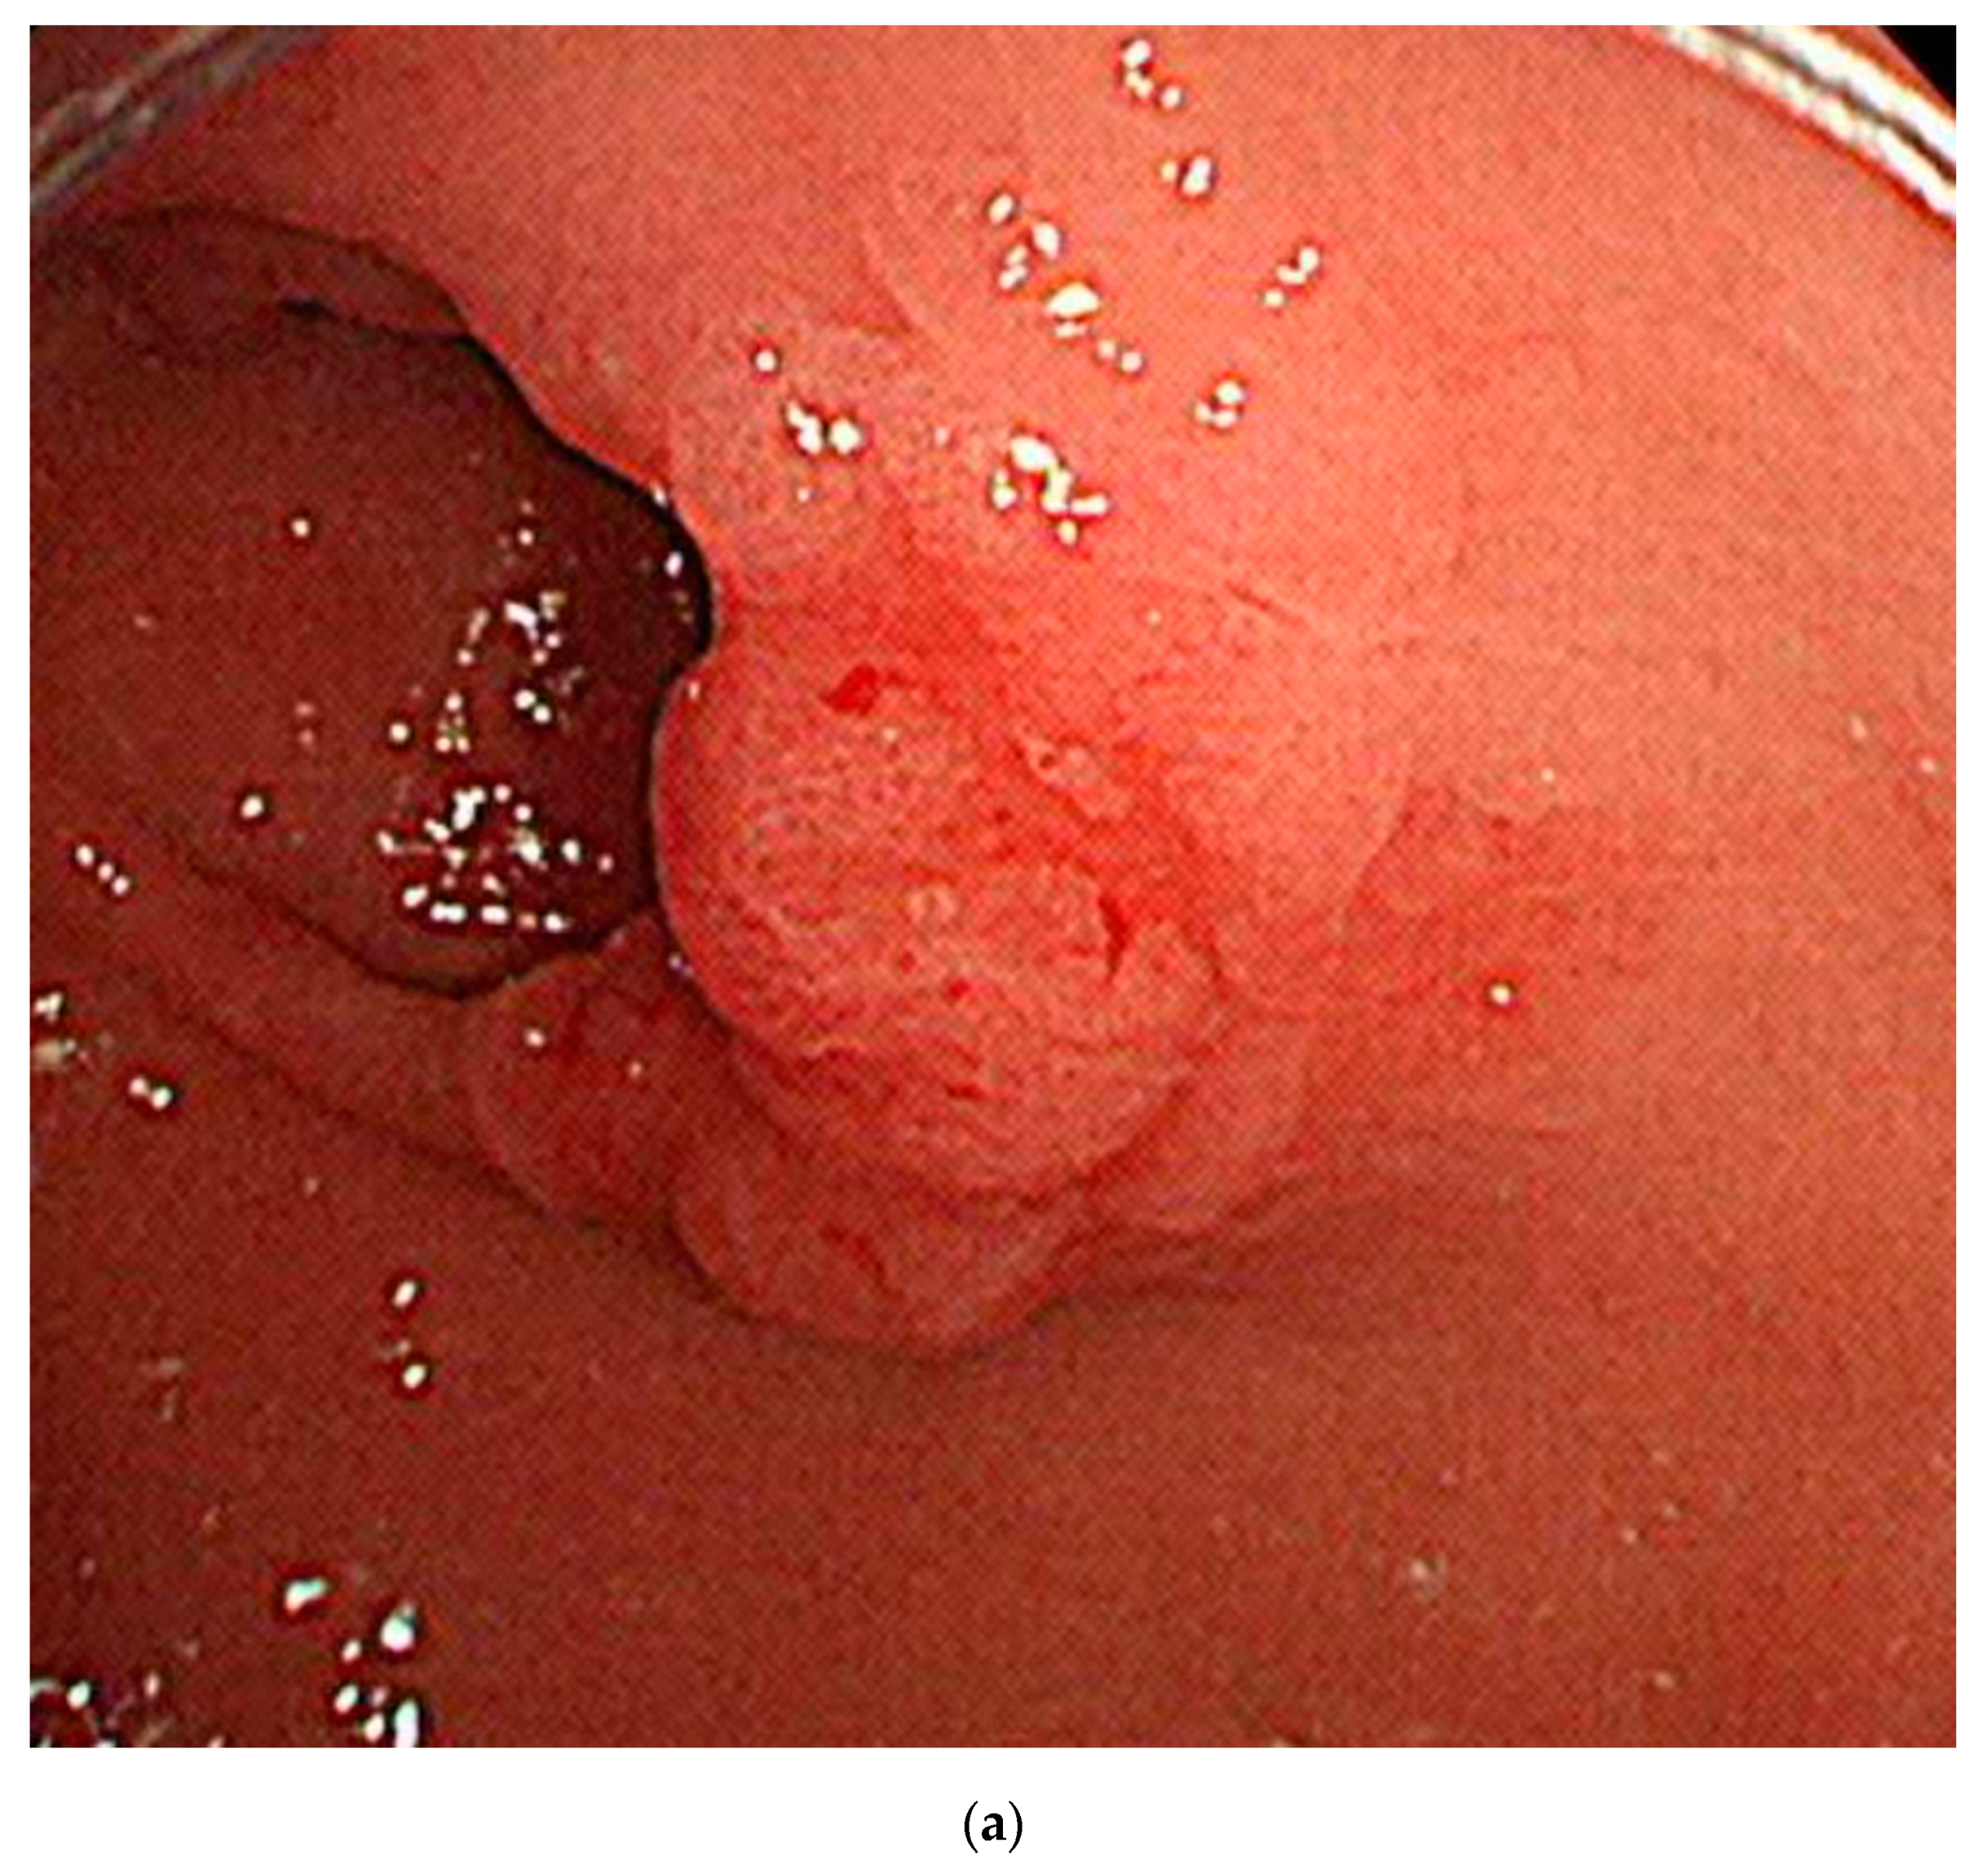

3.5. Attention Maps